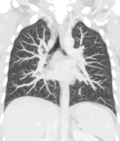

Lungs

A CT scan can be used for detecting both acute and chronic changes in the lung parenchyma, the tissue of the lungs.[41] It is particularly helpful because normal two-dimensional X-rays do not show such defects. A variety of techniques are used, depending on the suspected abnormality. For evaluation of chronic interstitial processes such as emphysema, and fibrosis,[42] thin sections with high spatial frequency reconstructions are used; often scans are performed both on inspiration and expiration. This special technique is called high resolution CT that produces a sampling of the lung, and not continuous images.[43]

Bronchial wall thickening can be seen on lung CTs and generally (but not always) implies inflammation of the bronchi.[44]

An incidentally found nodule in the absence of symptoms (sometimes referred to as an incidentaloma) may raise concerns that it might represent a tumor, either benign or malignant.[45] Perhaps persuaded by fear, patients and doctors sometimes agree to an intensive schedule of CT scans, sometimes up to every three months and beyond the recommended guidelines, in an attempt to do surveillance on the nodules.[46] However, established guidelines advise that patients without a prior history of cancer and whose solid nodules have not grown over a two-year period are unlikely to have any malignant cancer.[46] For this reason, and because no research provides supporting evidence that intensive surveillance gives better outcomes, and because of risks associated with having CT scans, patients should not receive CT screening in excess of those recommended by established guidelines.[46]